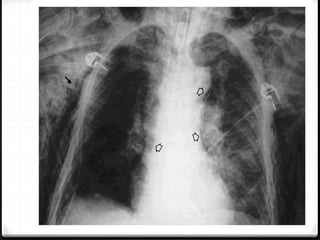

0 Pneumomediastinum

0 Pneumocardium

0 Hemopericardium

Pneumomediastinum

0 Cedera pada jalan nafas

0 Tingkat kematian tinggi

0 Jarang, 0.2%–8% dari seluruh kasus trauma thoraks

Pneumothoraks + pneumomedistinum + emfisema subkutis

Mediastinum dan Jantung 0Pneumomediastinum 0 Pneumocardium 0 Hemopericardium

Pneumomediastinum 0 Cedera padajalan nafas 0 Tingkat kematian tinggi 0 Jarang, 0.2%–8% dari seluruh kasus trauma thoraks